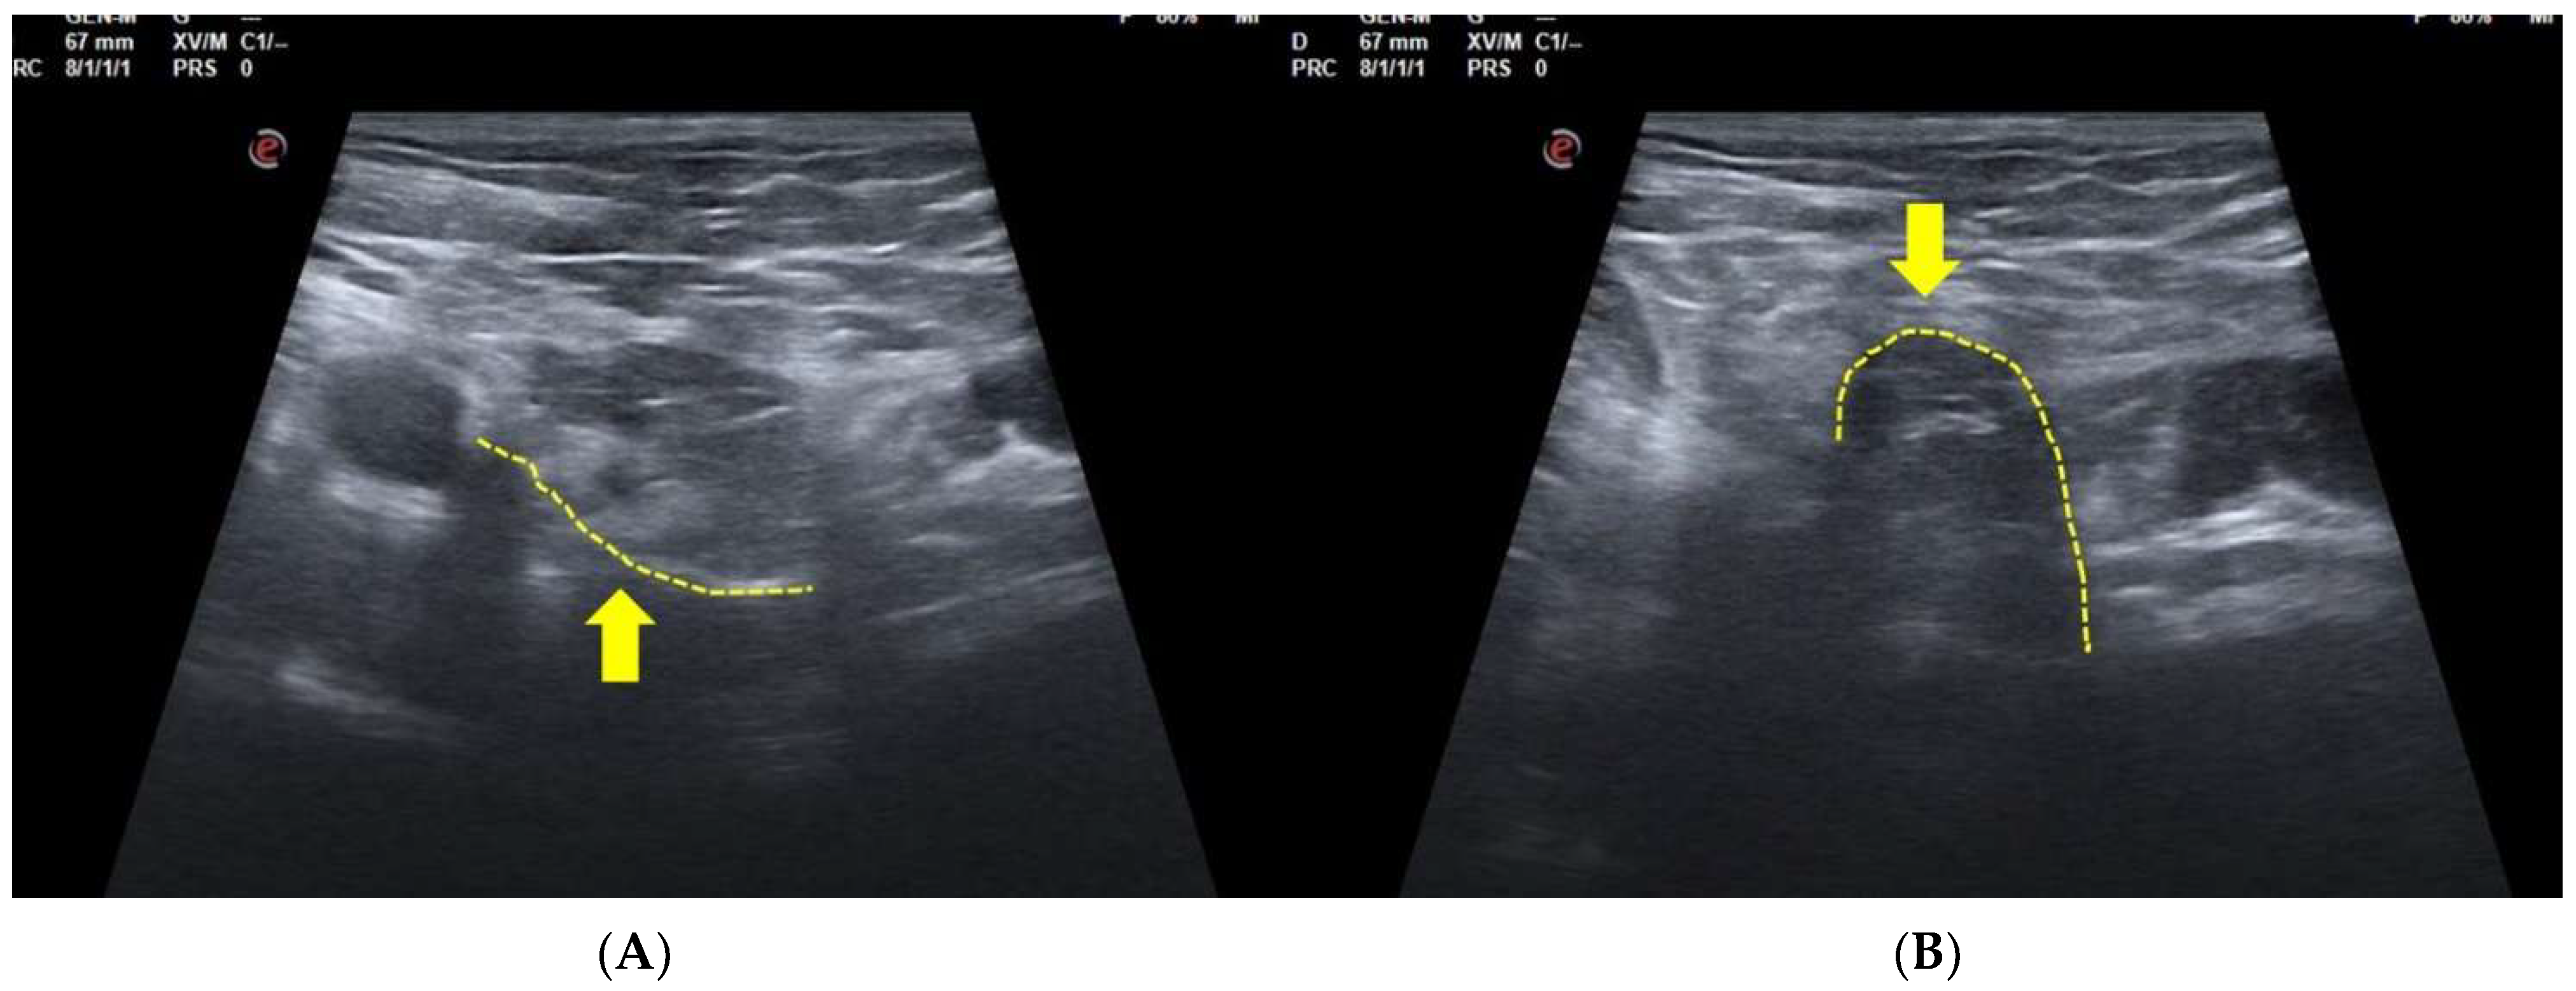

3.2. Dynamic Ultrasonography Examination